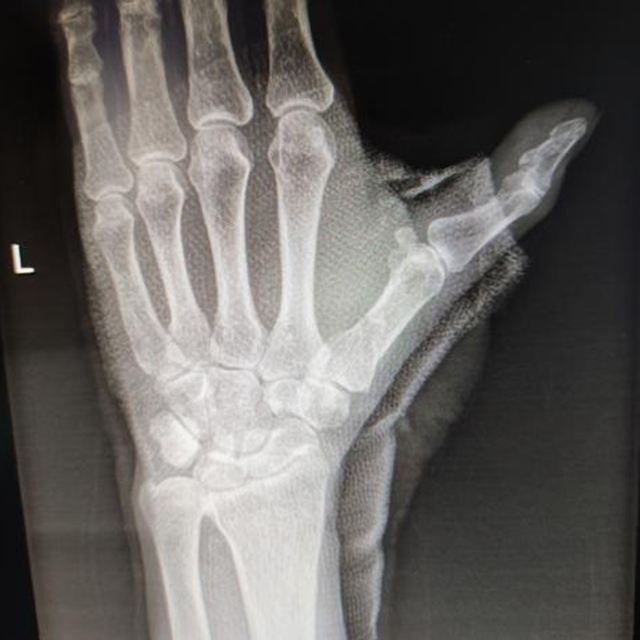

复位前

复位固定后